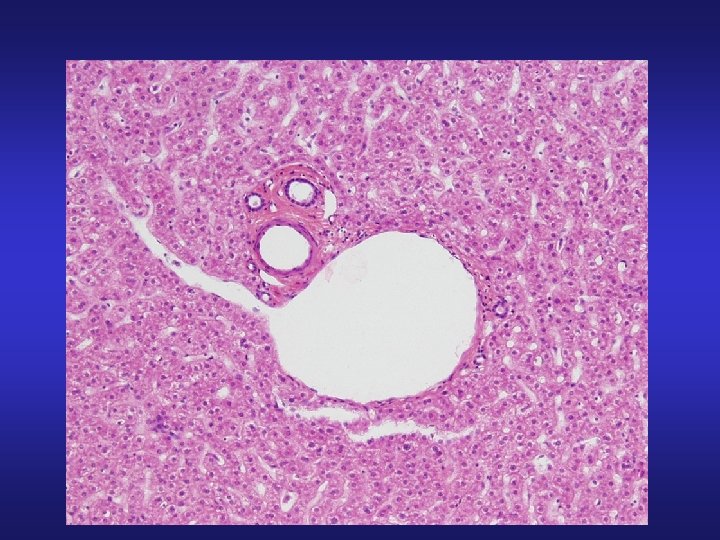

X-sectional view of the duodenum